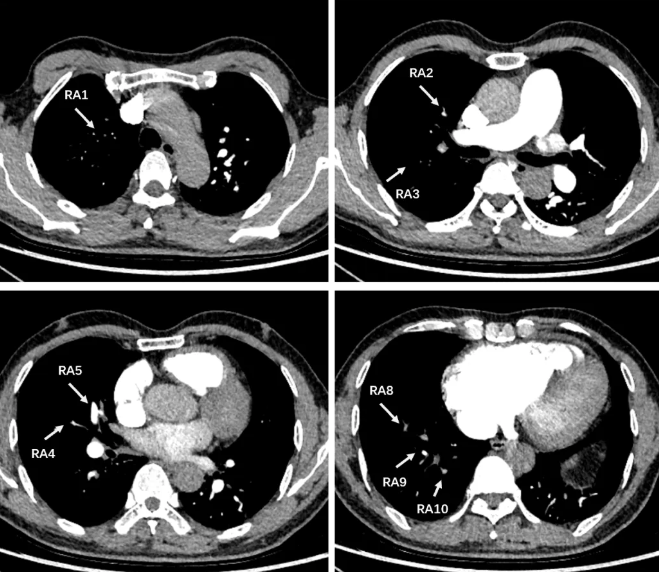

图6. 心脏超声 2025-3-19

患者拟诊CTEPH,按照CTEPH诊断流程(图3),完善CTPA(图4):右肺动脉分支远端显示不清,肺灌注显像(图5):左肺上叶及右肺大片状血流灌注减低/缺损,心脏超声(图6):右心扩大(右室前后径22mm,右房58×55mm)、TAPSE 24mm、三尖瓣轻度关闭不全(峰值流速4.5m/s)、肺动脉高压(重度,估测肺动脉收缩压99 mmHg)。右心导管检查结果示:mPAP 76/33(47)mmHg,CI 1.6L/min/m2,PVR12.3WU,SvO2:61.4%,RAP:8mmHg。肺动脉造影可见:双侧肺动脉及其分支广泛狭窄、闭塞病变,远端血流差,以右侧为重,血流多为0-1级(图7)。

图7 肺动脉造影